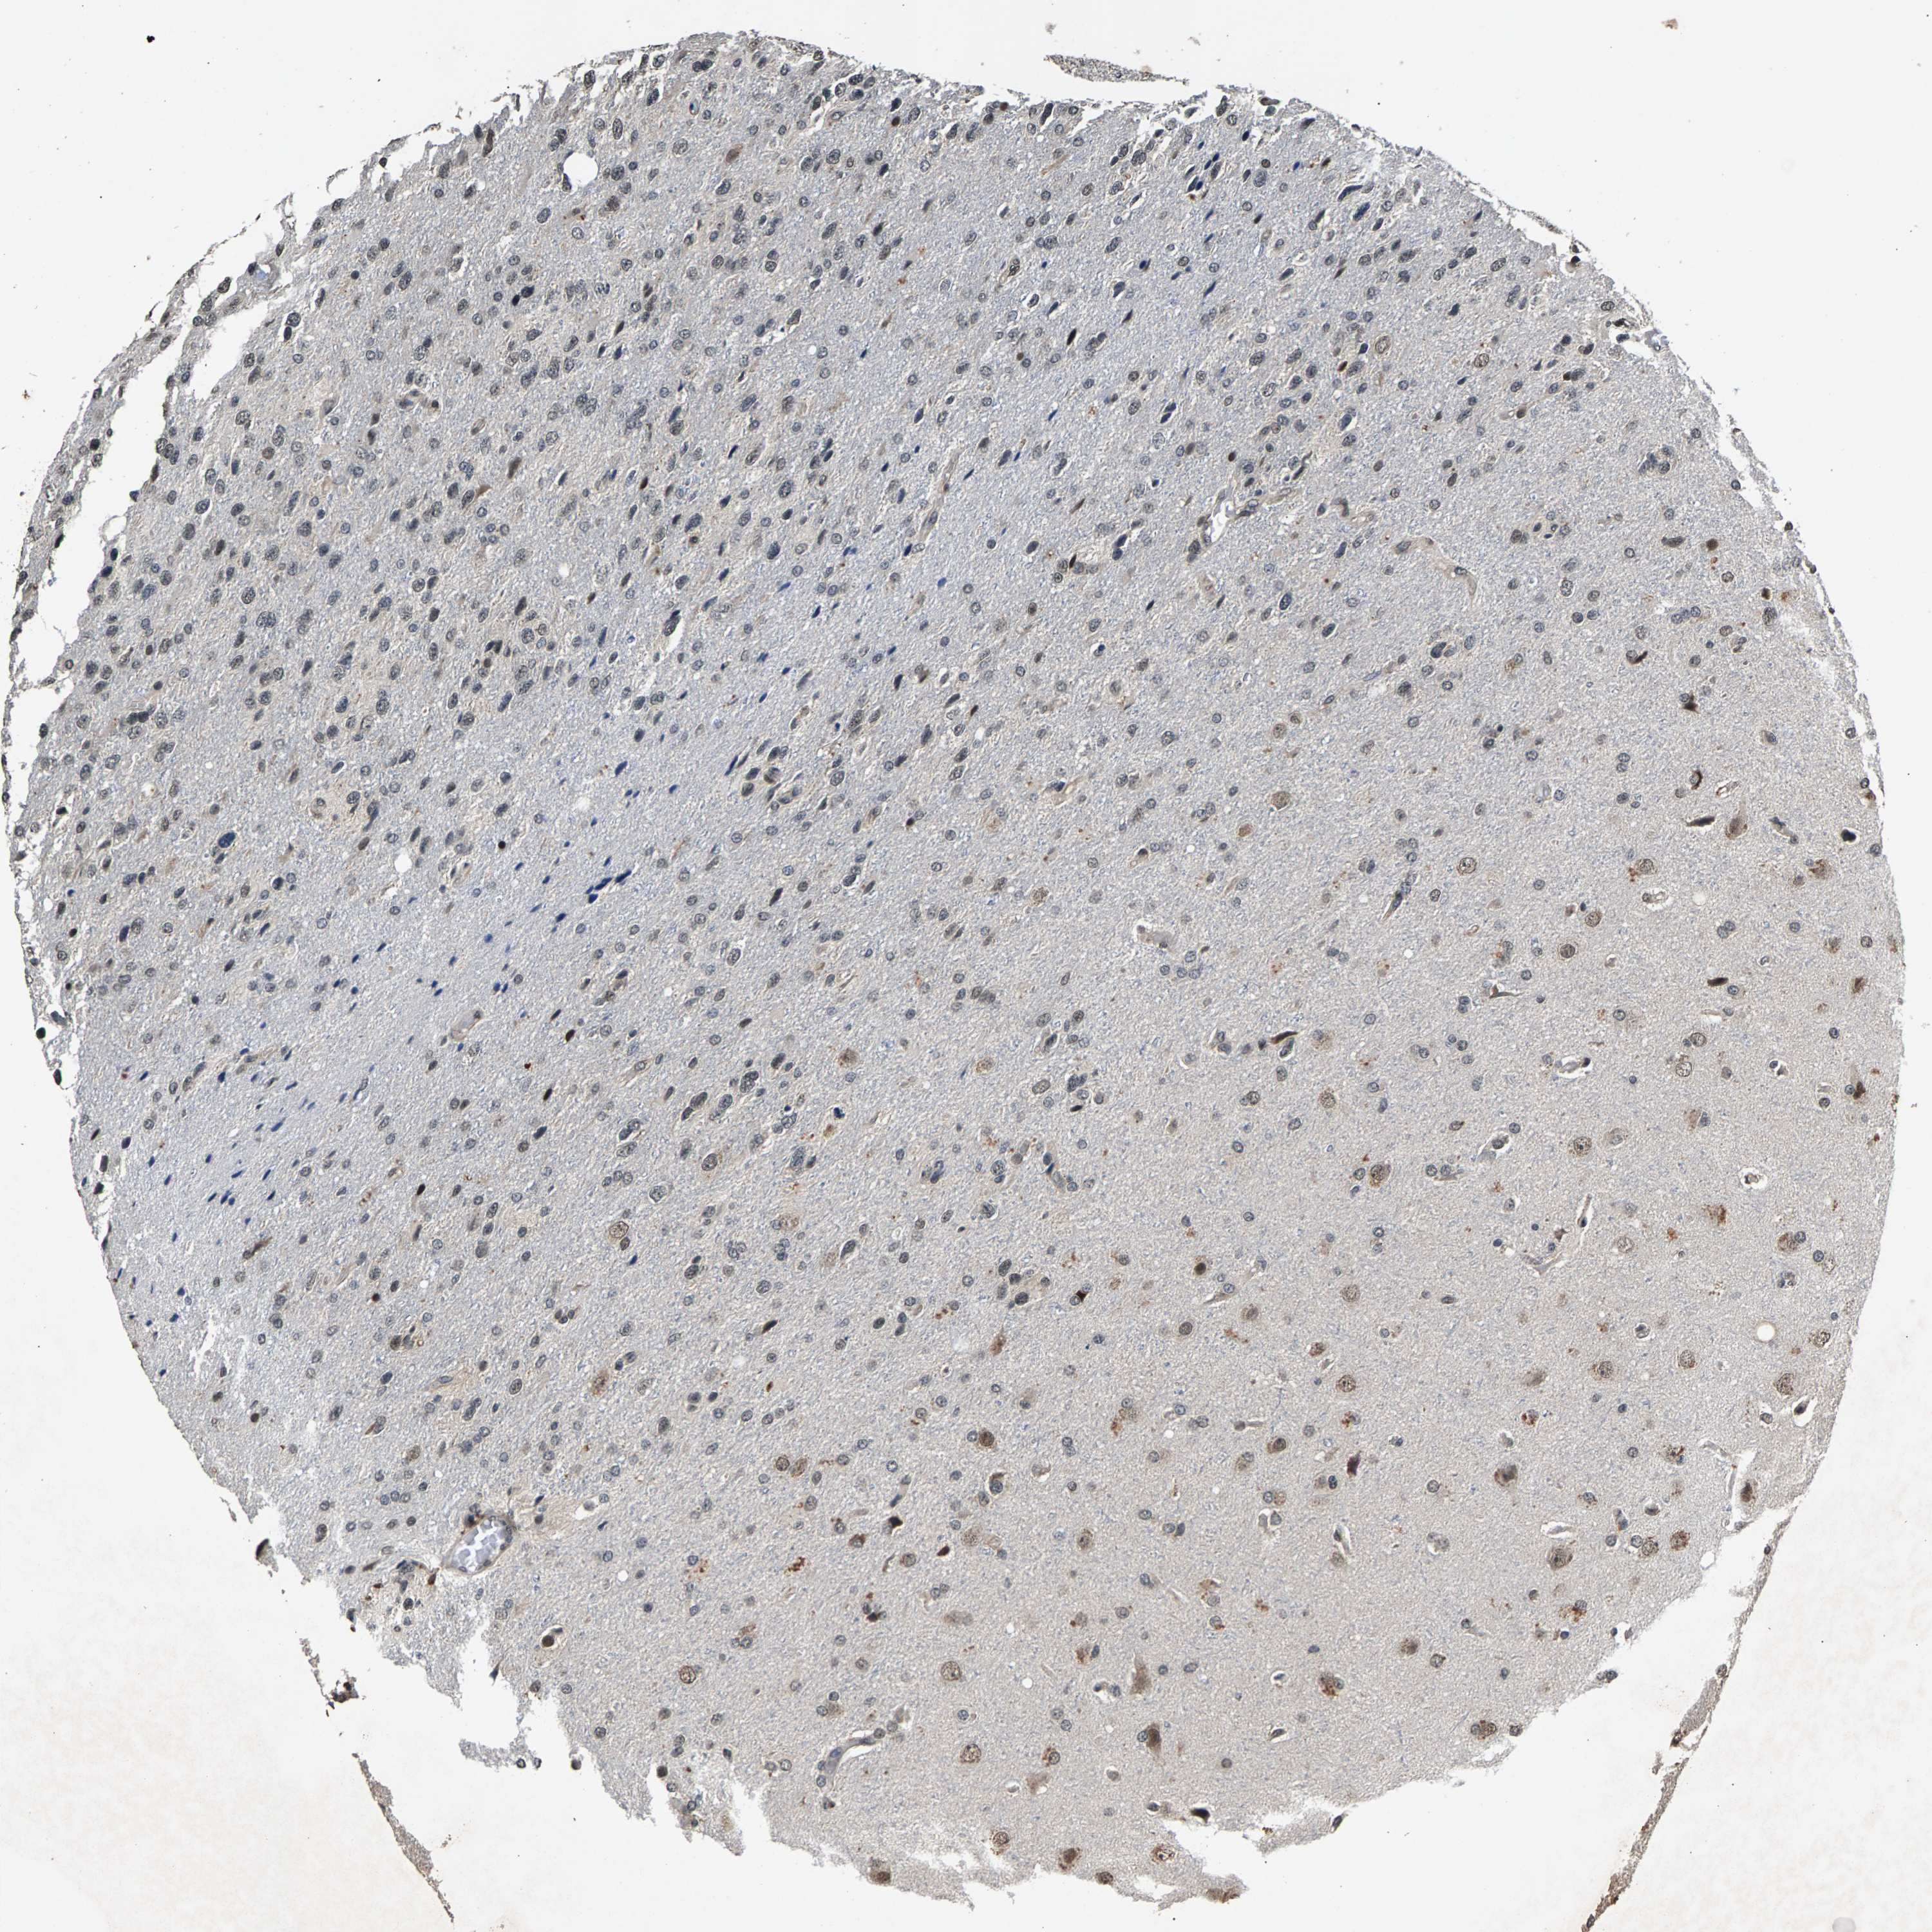

GLIOMA - Protein expressioni

A mouse-over function shows sample information and annotation data. Click on an image to view it in a full screen mode. Samples can be filtered based on level of antibody staining by selecting one or several of the following categories: high, medium, low and not detected. The assay and annotation is described here.

Note that samples used for immunohistochemistry by the Human Protein Atlas do not correspond to samples in the TCGA dataset.

Antibody stainingi

Antibody staining in the annotated cell types in the current human tissue is reported as not detected, low, medium, or high, based on conventional immunohistochemistry profiling in selected tissues. This score is based on the combination of the staining intensity and fraction of stained cells.

Each image is clickable and will lead to virtual microscopy that enables deeper exploration of all samples and also displays staining intensity scores, fraction scores and subcellular localization as well as patient and tissue information for each sample.

Antibody HPA019232

Antibody HPA021497

Antibody HPA021768

Staining

High

Medium

Low

Not detected

Intensity

Strong

Moderate

Weak

Negative

Quantity

>75%

75%-25%

<25%

None

Glioma, malignant, High grade

Glioma, malignant, Low grade